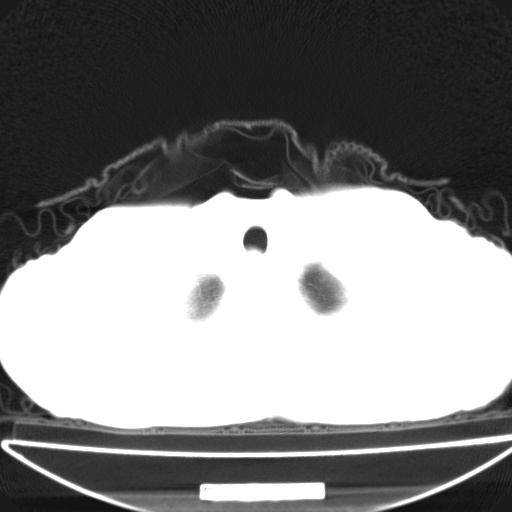

以下是引用jsgdoctor在2008-11-6 22:12:00的发言:[br]右主支气管壁明显增厚,管腔狭窄.考虑为右侧中央型肺癌伴阻塞性炎症\\肺脓肿.

以下是引用zjzjr在2008-11-6 20:25:00的发言:[br]中心型肺ca,合并阻塞性肺炎

以下是引用zsl6918在2008-11-6 19:43:00的发言:[br]右侧中心性肺癌(鳞癌)